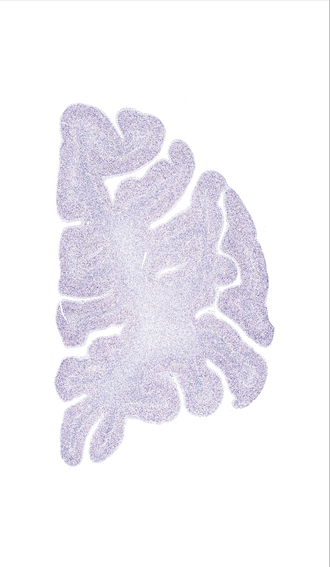

Hi-Resolution Sections · Cells (Nissl Staining) · Virtual Microscopy

Frontal sections (Nissl) from the Atlas Brain:

Microscopy